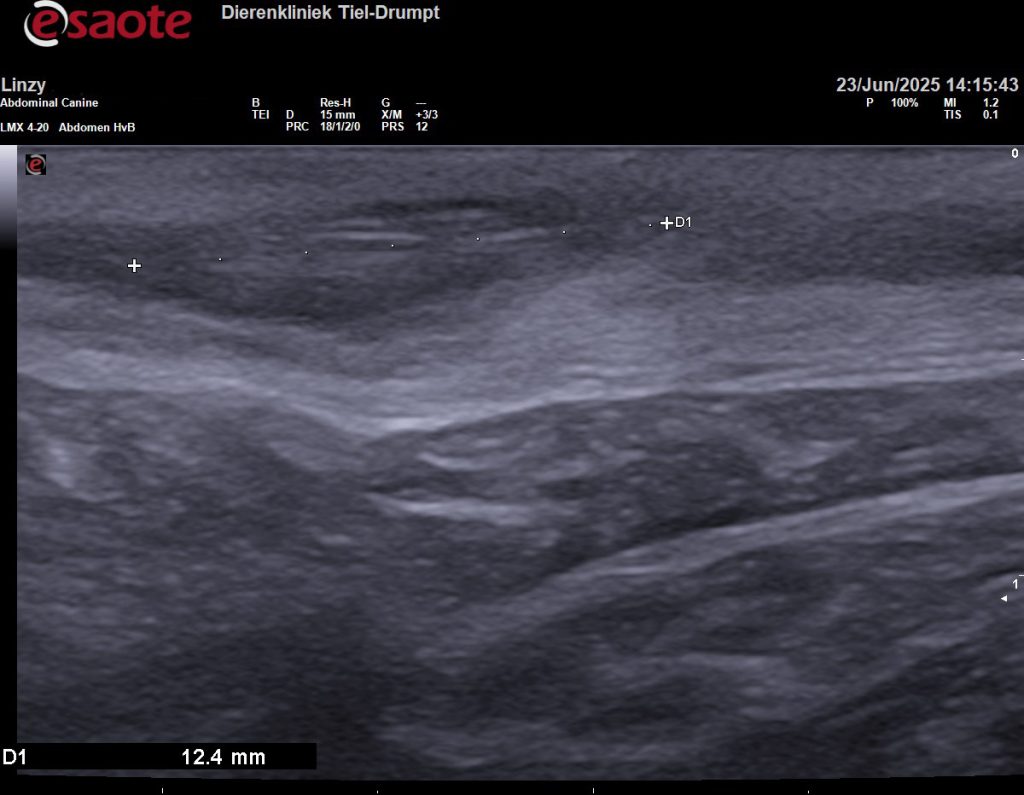

Om meer duidelijkheid te hebben, om te voorkomen dat we voor niks chirurgisch zouden ingrijpen, hebben we de plek eerst bekeken met een echo. Gelukkig hebben we ook een echokop voor zeer veel detail en het beeld bleek eigenlijk heel goed bij een grasaar te passen.

Om zeker te weten dat we alles hadden is het weefsel geopend, voordat we de wond gingen sluiten. In eerste instantie leek het alsof er geen grasaar in het weefsel zat. Maar dit liet maar weer zien hoeveel ons echoapparaat kan vergroten, want op de echobeelden is de diameter van de grasaar 1,5 millimeter en 12,4 millimeter lang. Na een paar sneden vonden we het steekkanaal en de daadwerkelijke grasaar.